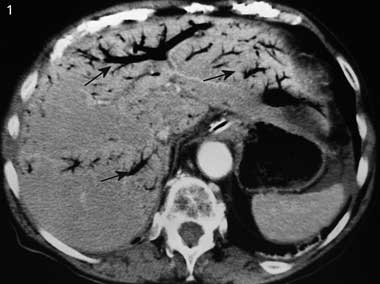

A 90-year-old woman was admitted with acute vomiting for the previous 24 hours and acute, diffuse, intense abdominal pain. Her medical history included atrial fibrillation and hysterectomy. Clinical examination revealed a generally distended, tender, tympanic and silent abdomen. Blood pressure was 98/54 mmHg; her pulse was irregular at 67 beats per minute. A plain x-ray of the abdomen revealed bowel distension without air–fluid levels. A computed tomography scan of the abdomen showed the presence of gas in the portal venous system (Box 1) and the intestinal wall (Box 2). At laparotomy, 142 cm of necrotic ileum was removed. The postoperative course was uneventful, and the patient was discharged 1 month later.

The precise mechanism for formation of gas in the portal venous system is uncertain.1 The primary factors that favour this development are intestinal wall alterations, bowel distension and intra-abdominal sepsis.1 In many cases, two or three of these circumstances may coexist. In 15% of cases, the cause of air in the portal venous system remains unknown.1 Several conditions, such as perforated ulcer, interventional procedures, trauma, and infectious or inflammatory abdominal diseases, but most commonly intestinal ischaemia (as in our patient), can cause alterations of the gastric and bowel wall, permitting the passage of intraluminal gas into the portal venous system.1-3 Gas from the intestinal lumen passes through the intestinal wall and travels via the small mesenteric veins and the superior or inferior mesenteric vein to the portal venous system. Further, the presence of gas simultaneously in the portal venous system and intestinal wall seems to be specific to intestinal ischemia.4